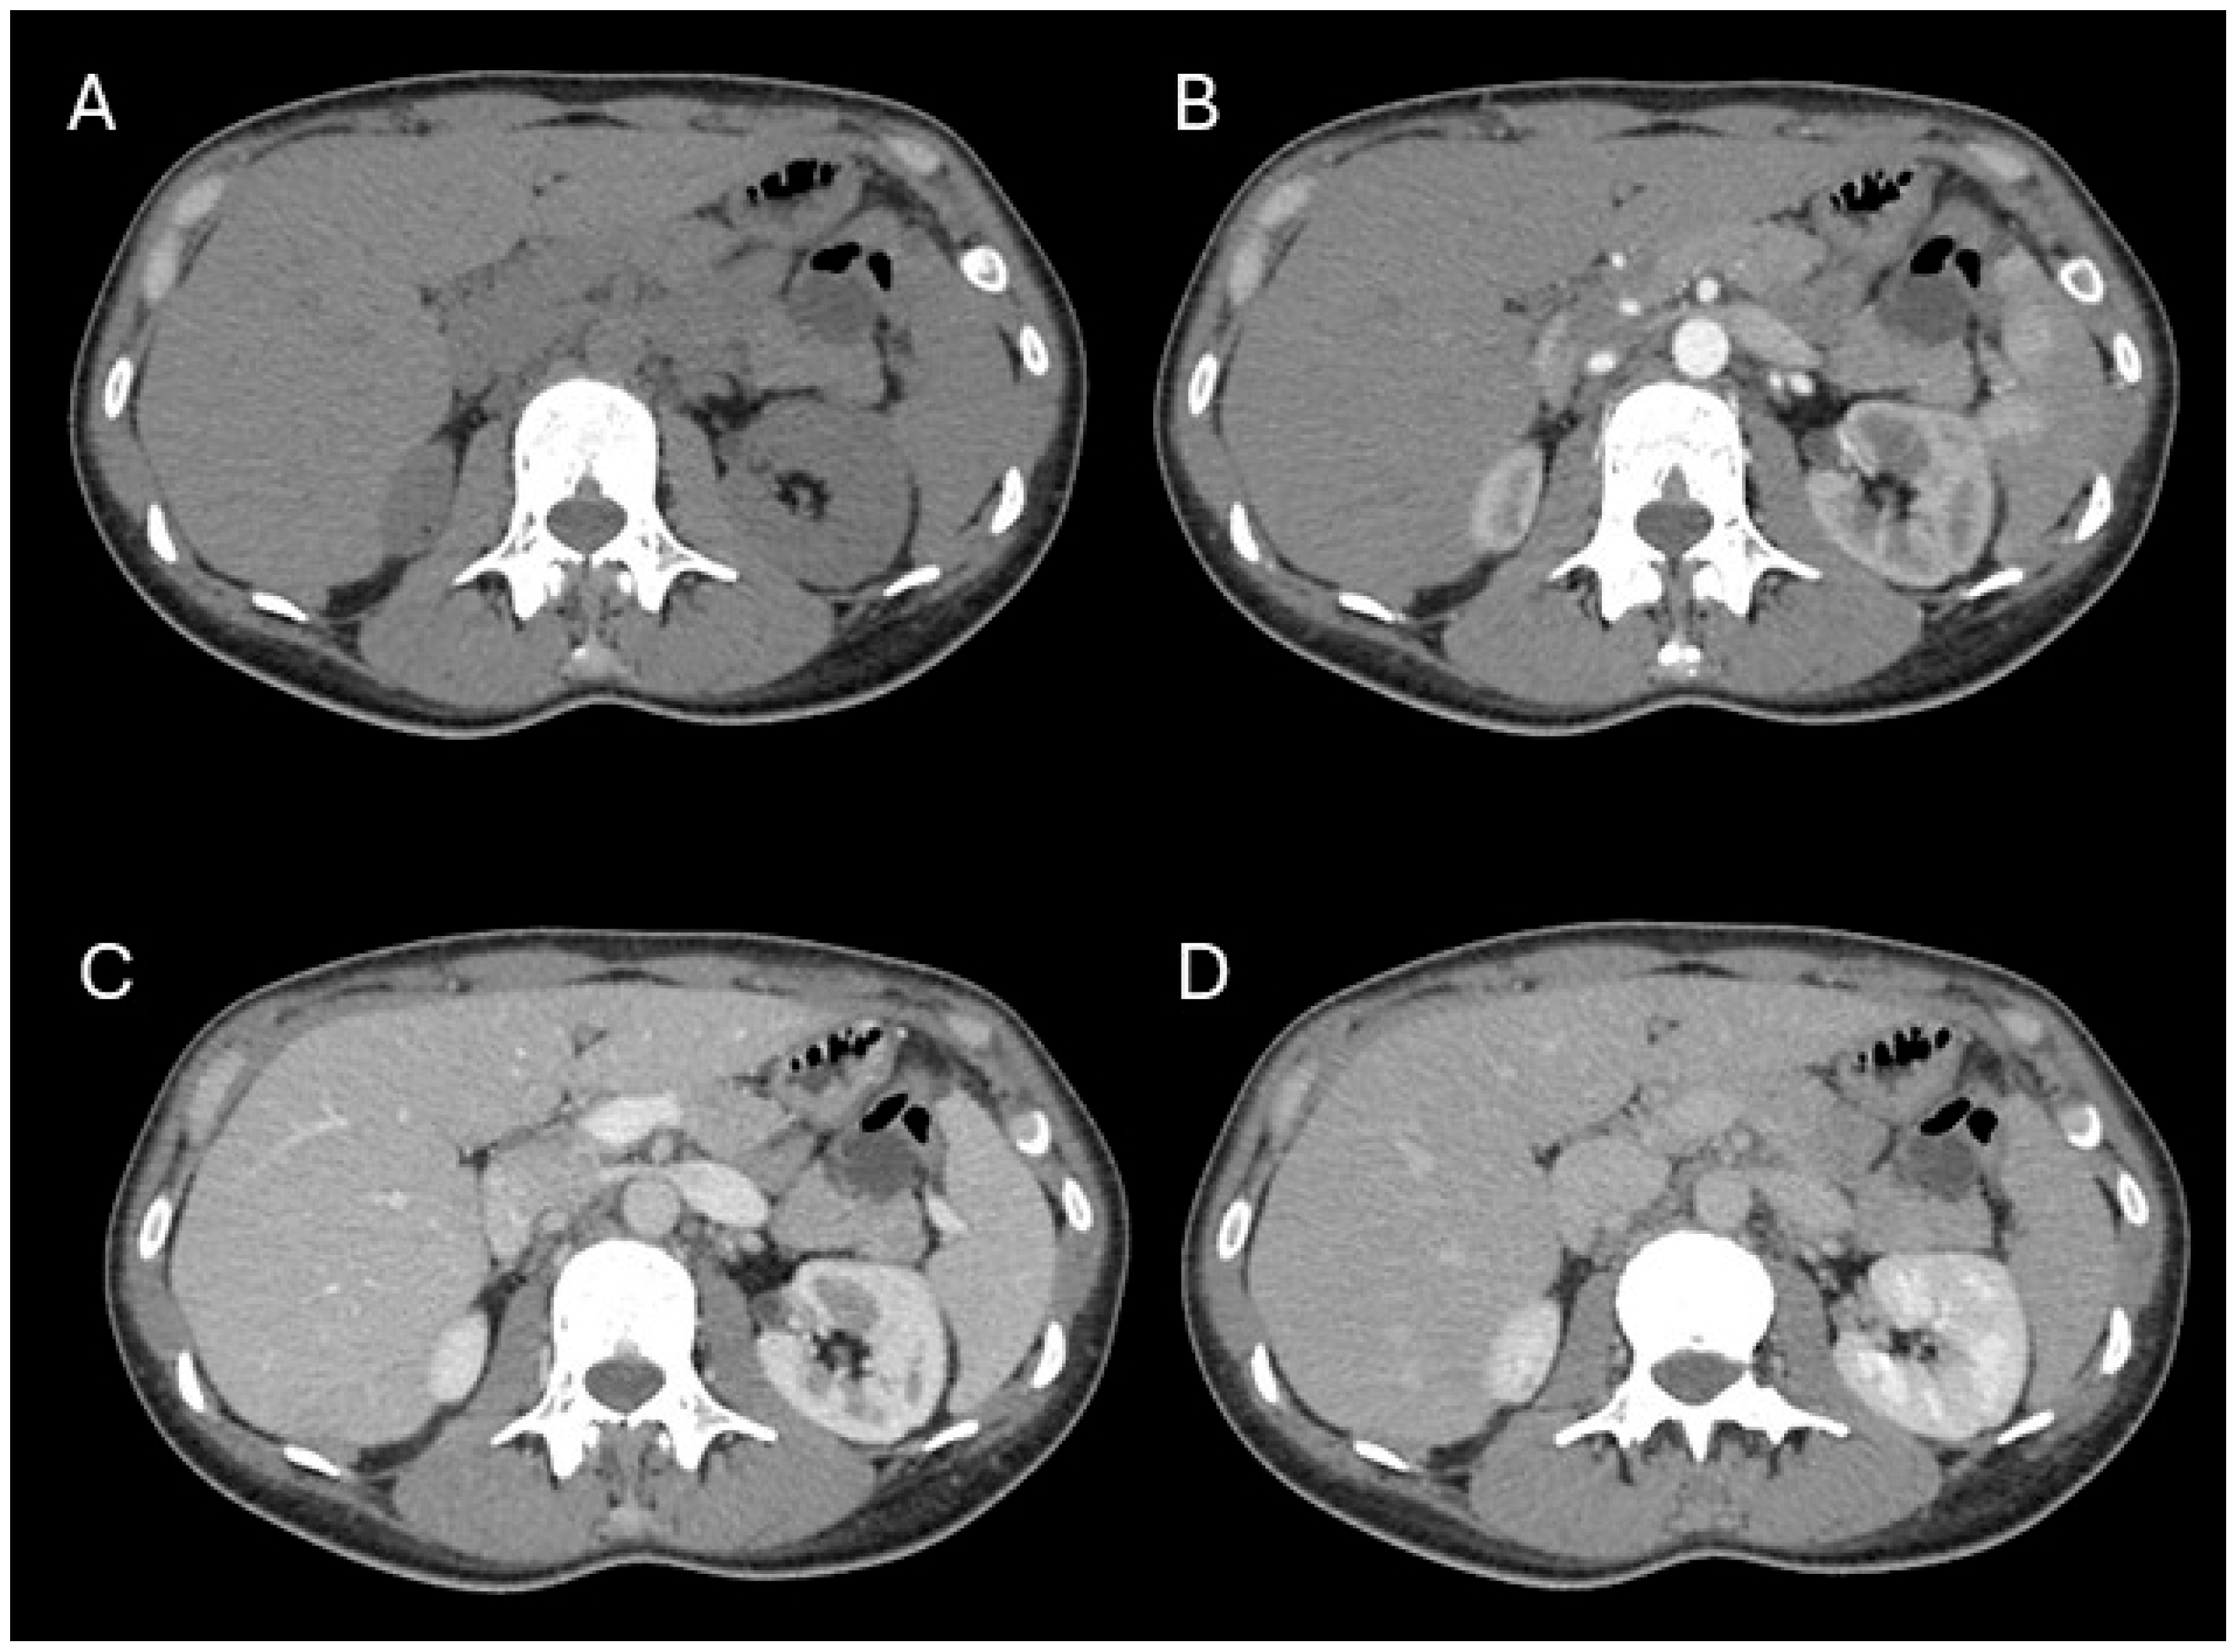

Background: Pancreatic hamartoma (PH) is an exceptionally rare, benign, mass-forming lesion accounting for less than 1% of all pancreatic tumors. Its rarity and non-neoplastic nature contribute to significant diagnostic challenges, often leading to misclassification as malignant disease. This study presents a case of PH and a systematic review of all reported cases, with emphasis on histopathological and imaging characteristics. Methods: A comprehensive electronic search of PubMed, Scopus, and Web of Science was conducted up to 1 April 2025, to identify eligible case reports and series. Results: We describe a 37-year-old woman with a cystic lesion of the pancreatic tail, ultimately confirmed histologically as a cystic pancreatic hamartoma following distal pancreatectomy with splenectomy, with an uneventful postoperative course. Of 687 screened studies, 51 met the inclusion criteria, comprising 77 cases (68 adults, 9 pediatric). PHs occurred most frequently in males (52.9%), with a mean age of 59.5 ± 12.9 years, and were often asymptomatic (57.4%). The pancreatic head was the most common site (52.9%). On MRI, PHs typically exhibited low T1-weighted and high T2-weighted signal intensity, with no FDG uptake (82%) and moderate or no restriction on DWI, distinguishing them from neuroendocrine tumors (NETs). Histologically, most lesions were solid (64.7%) or solid–cystic (35.3%), with low spindle cell cellularity and absent Langerhans islets. Conclusions: Low T1WI signal and moderate DWI signal are the key features distinguishing PHs from NETs. Incorporating these findings with EUS-FNA and immunohistochemistry can support a provisional diagnosis and help avoid unnecessary radical surgery.